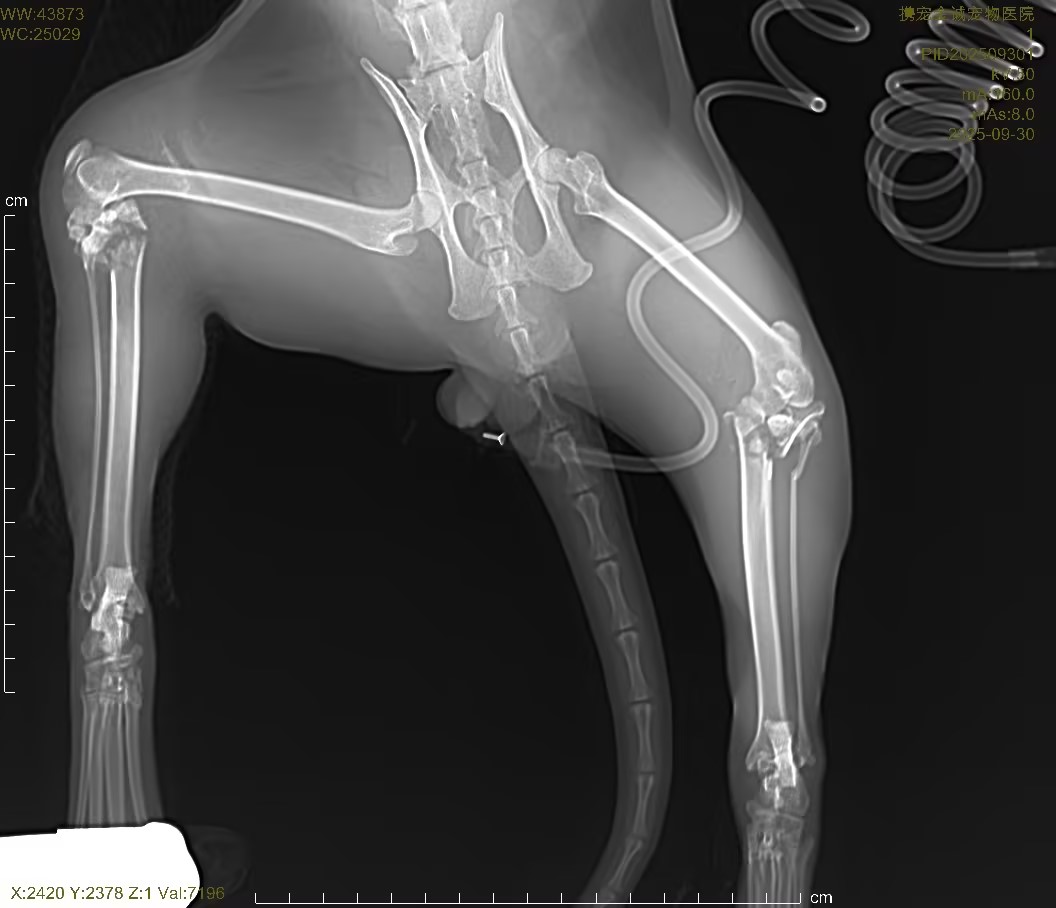

3.影像学检查(X 光)

对患猫胸腔、腹腔、全身骨骼进行数字化 DRX 光正侧位摄片,明确高空坠落所致骨骼、胸腔、腹腔脏器损伤情况:

骨骼系统

脊柱、四肢长骨可见骨连续性中断、骨皮质错位,确诊高空坠落所致外伤性骨折,骨折端无明显粉碎性重度破坏,适合微创固定修复;

骨盆结构轻度移位,无骨盆环破裂、无脏器卡压,无开放性骨折表现;

关节腔结构清晰,无脱位、无关节腔内积液。

胸腔脏器

双肺纹理略增粗,无气胸、无血胸、无肺挫伤重度实变;

心影轮廓正常,无胸腔积液、无纵隔移位,无致命性胸腔损伤。

腹腔脏器

腹腔内脏器位置正常,无游离气体、无腹腔积液,排除胃肠道穿孔、膀胱破裂等急腹症;

肝、肾轮廓未见明显破裂、移位,无急腹症影像学征象。

X 光结论:确诊四肢 / 躯干外伤性骨折,无气胸、血胸、腹腔破裂等致命性继发损伤,为骨 02 胶水微创骨折固定手术提供明确影像学依据,手术指征明确、安全性可评估。